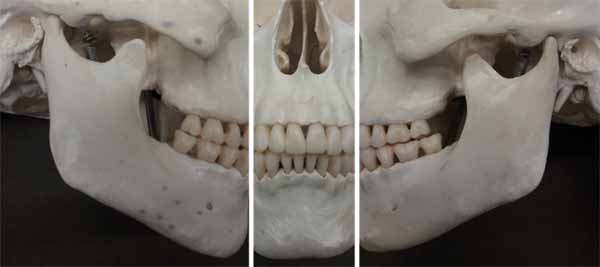

パノラマX線写真を確認する際に最初に考慮すべきことのひとつは、画像が撮影された視点です。撮影中、放射線源と画像受容器は患者の周囲を回転するため、画像のさまざまな部分が異なる投影から生じます。パノラマ画像を見る最も簡単な方法は、前部を前後方向の投影として見ながら、右側と左側を横方向の投影として見ることです(画像25を参照)。

パノラマX線は首、中顔面、顎の両方の概要画像であるため、口腔内全長画像よりも多くの硬組織構造が含まれます。これらすべての構造を識別する際には、さまざまな構造を区別し、これらをあらゆる可能性のある病理と区別できるようにするために、正常な人体の解剖学に関する知識を持っていることが非常に役立ちます。頭蓋骨内のさまざまな構造の位置は、ほとんどの場合、パノラマ画像内の位置に反映されます。翼状突起は上顎の後ろ、顎関節は側頭骨の下方、眼窩は上顎洞の上方に見える、などと予想されます。なぜなら、それがこれらの構造の自然な解剖学的位置だからです。これらの構造がパノラマ画像で確認できることも事実です(画像25および26を参照)。